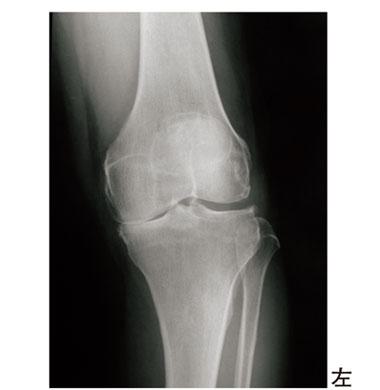

75歳の女性。左膝痛を訴え、関節可動域が伸展-10°、屈曲95°に制限されている。来院時のエックス線写真を示す。膝関節拘縮に対する治療で正しいのはどれか。

1

CPMを行う。

2

大腿を固定して伸張を加える。

3

疼痛を感じるレベルの矯正力を加える。

4

動的膝装具は用いない。

5

連続ギプス法では1日ごとに5°ずつ矯正位を強める。